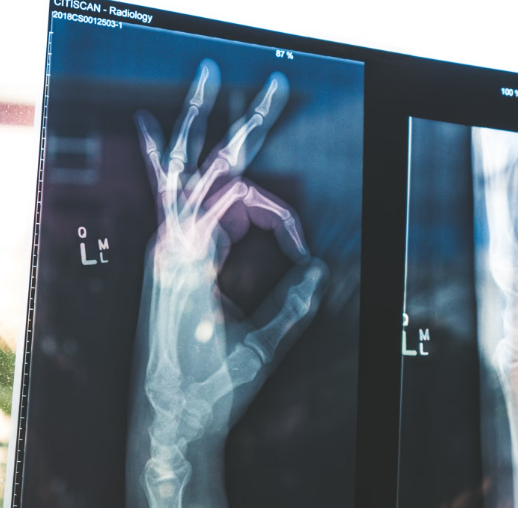

손가락 저림의 다양한 원인

1. 손목터널증후군 (수근관증후군)

손목터널증후군은 손목의 중간 신경이 압박되면서 발생하는 질환입니다. 주로 손목을 많이 사용하는 직업이나 활동을 할 때 발생하며, 손가락(특히 엄지, 검지, 중지)에서 저림이나 통증이 느껴질 수 있습니다.